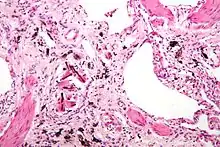

Asbestosis is the scarring of lung tissue (beginning around terminal bronchioles and alveolar ducts and extending into the alveolar walls) resulting from the inhalation of asbestos fibers. There are two types of fibers: amphibole (thin and straight) and serpentine (curly). All forms of asbestos fibers are responsible for human disease as they are able to penetrate deeply into the lungs. When such fibers reach the alveoli (air sacs) in the lung, where oxygen is transferred into the blood, the foreign bodies (asbestos fibers) cause the activation of the lungs' local immune system and provoke an inflammatory reaction dominated by lung macrophages that respond to chemotactic factors activated by the fibers.[20] This inflammatory reaction can be described as chronic rather than acute, with a slow ongoing progression of the immune system attempting to eliminate the foreign fibers. Macrophages phagocytose (ingest) the fibers and stimulate fibroblasts to deposit connective tissue.

Due to the asbestos fibers' natural resistance to digestion, some macrophages are killed and others release inflammatory chemical signals, attracting further lung macrophages and fibrolastic cells that synthesize fibrous scar tissue, which eventually becomes diffuse and can progress in heavily exposed individuals. This tissue can be seen microscopically soon after exposure in animal models. Some asbestos fibers become layered by an iron-containing proteinaceous material (ferruginous body) in cases of heavy exposure where about 10% of the fibers become coated. Most inhaled asbestos fibers remain uncoated. About 20% of the inhaled fibers are transported by cytoskeletal components of the alveolar epithelium to the interstitial compartment of the lung where they interact with macrophages and mesenchymal cells. The cytokines, transforming growth factor beta and tumor necrosis factor alpha, appear to play major roles in the development of scarring inasmuch as the process can be blocked in animal models by preventing the expression of the growth factors.[21][22] The result is fibrosis in the interstitial space, thus asbestosis.

Figure A shows the location of the lungs, airways, pleura, and diaphragm in the body. Figure B shows lungs with asbestos-related diseases, including pleural plaque, lung cancer, asbestosis, plaque on the diaphragm, and mesothelioma..jpg.webp) Extensive fibrosis of pleura and lung parenchyma